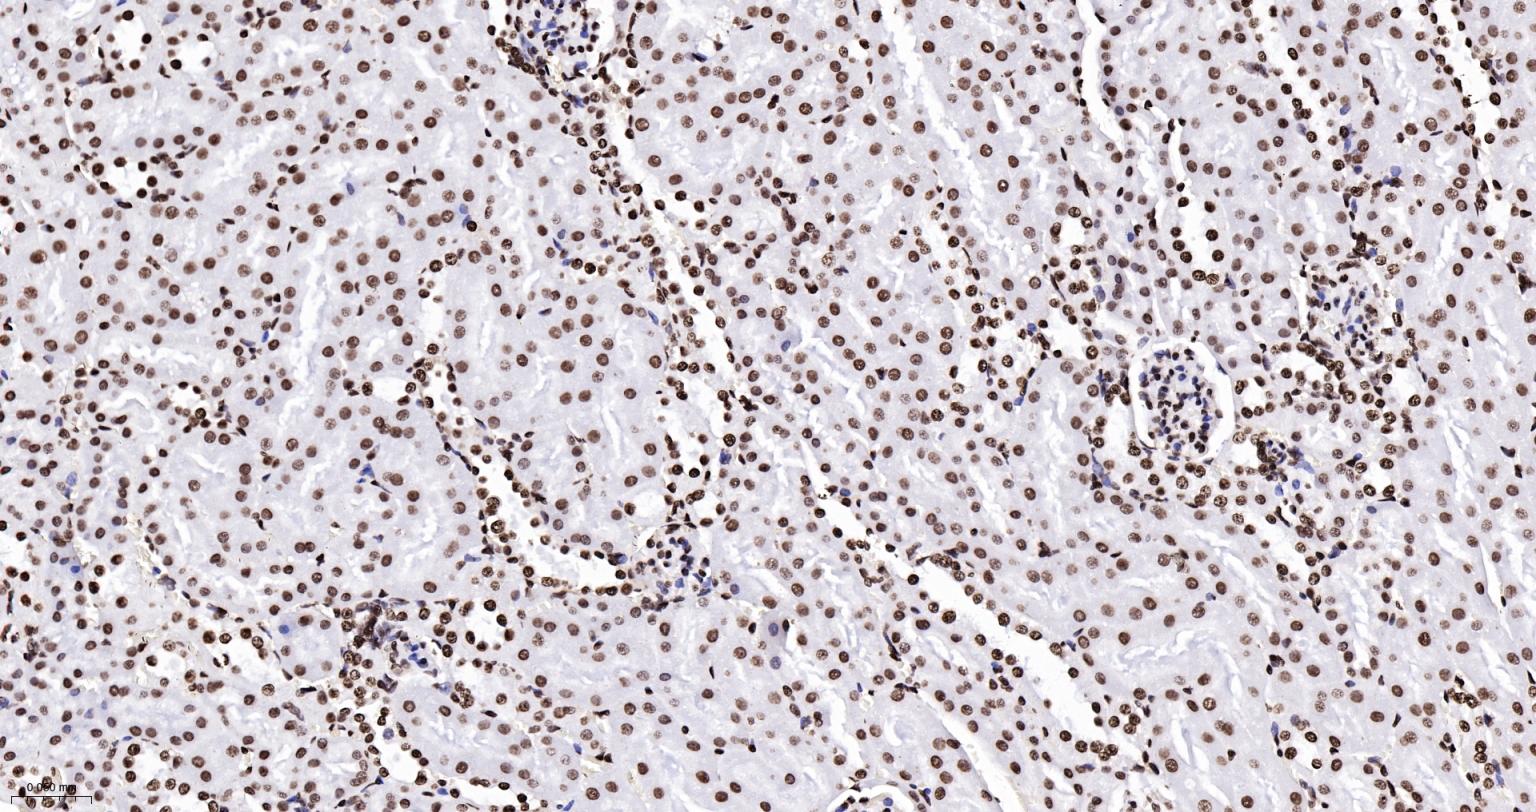

Paraformaldehyde-fixed, paraffin embedded Mouse Kidney; Antigen retrieval by boiling in sodium citrate buffer (pH6.0) for 15 min; Antibody incubation with Histone H2A.X Monoclonal Antibody, Unconjugated(bsm-61080R) at 1:200 overnight at 4°C, followed by conjugation to the SP Kit(Rabbit, SP-0023) and DAB (C-0010) staining.